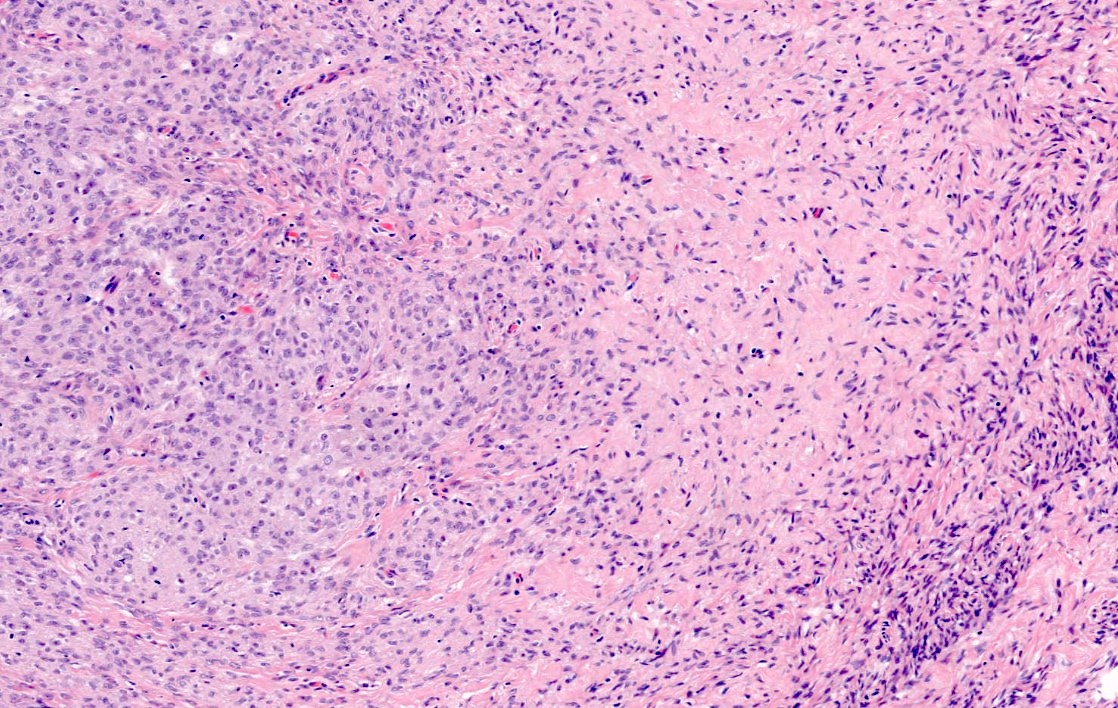

Microscopic (histologic) description

- Predominant population of cells showing ovoid to round nuclei and pale gray cytoplasm, which can be abundant

- Minor component of the tumor may have spindled nuclei, reflecting overlap between fibroma and thecoma

- Indistinct cell membranes impart a syncytial appearance

- Diffuse or nodular growth pattern

- Absent or minimal nuclear atypia

- Mitotic rate usually < 5/10 high power fields

- Hyaline plaques

- Cytoplasmic lipid vacuoles may be present but are not essential

- May show aggregates of cells with brightly eosinophilic cytoplasm (lutein cells)

- Calcification is more common in young patients (Int J Gynecol Pathol 1988;7:343)

- Uncommon features include keloid-like sclerosis, nuclear grooves, bizarre nuclear atypia (Am J Surg Pathol 2014;38:1023)

- Rarely contains a minor component of sex cord elements (Int J Gynecol Pathol 1983;2:227)

- Malignant thecoma: very rare, diagnosis requires diffuse moderate to severe nuclear atypia and high mitotic rate (> 4/10 high power fields) (Am J Surg Pathol 2011;35:e15)

Microscopic (histologic) images

Contributed by Victoria Collins, M.D., Tamara Kalir, M.D., Ph.D., AFIP and @SeoparjooAzmel on Twitter